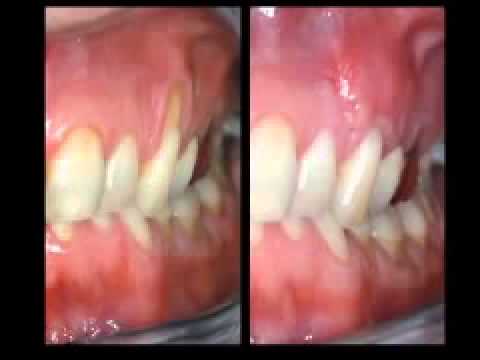

Лечение при опускании десен Стоматология СумыСкачать